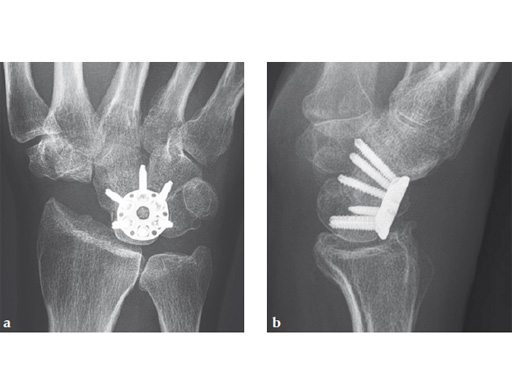

Fig 6ab Final appearance of fixed plate.

Fig 7ab No impingement of the plate against the dorsal rim of the radius in extension.